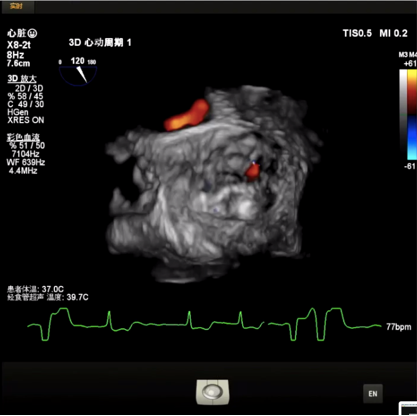

在CUSP OVERLAP投照角度下进行瓣膜释放,释放过程中杨毅宁教授密切关注患者各项体征指标以及各器材位置情况,稳步操作最终达到预计位置精准定位,术后跨瓣压差即刻降低至0,患者双侧冠脉灌注良好,无反流,超声检测血流动力学明显改善,手术取得圆满成功。 中心简介 新疆维吾尔自治区人民医院始建于1934年,是一所集医疗、教学、科研、预防、保健和社区卫生服务为一体的大型综合性“三级甲等医院”。曾先后荣获“全国文明单位”、“全国百佳医院”、“全国五·一劳动奖状”、“全国卫生系统先进集体”、“全国万名医师支援农村卫生工程先进集体”、“全国十大百姓放心医院”、“全国卫生系统思想政治工作先进集体”、“自治区民族团结进步模范单位”等荣誉称号,是中国医院竞争力·顶级医院100强。 专家简介 杨毅宁 新疆维吾尔自治区人民医院 医学博士,博士生导师,教授、主任医师。 现任新疆维吾尔自治区人民医院党委副书记、院长。2004年和2007年分别于新加坡国立大学医院导管室和德国Mainz Johannes Gutenberg大学临床医院心内科研修冠状动脉介入治疗。目前研究方向为冠心病、先天性心脏病及瓣膜病的介入治疗及相关基础研究。国务院特殊津贴专家,新疆自然科学专家。2017年入选“国家百千万人才工程”并被授予“有突出贡献中青年专家”荣誉称号,第十二届“中国医师奖”获得者,先后入选教育部新世纪优秀人才计划,自治区“天山雪松计划”科技创新领军人才后备,“天山英才”培养计划第一层次。 主持国家重点研发计划1项,国家自然科学基金6项,教育部新世纪优秀人才计划项目1项,自治区级科研项目14项,参与国家自然科学基金、国家“十一五”计划子课题及横向课题、自治区重大专项等20余项研究。以第一作者或通讯作者身份发表学术论文250余篇,其中SCI收录论文60篇,CSCD收录论文174篇。主参编专著16部,荣获自治区科技进步奖10项,其中一等奖4项、二等奖6项,荣获中华医学科技奖2项,2020年被评为自治区“最美科技工作者”。在临床工作中不断开拓创新,年均完成经皮冠状动脉介入治疗(PCI)2000余例,先心病介入封堵术350余例,积极开展和推广IVUS、OCT、远隔缺血适应治疗等新技术的临床应用。在疑难危重症治疗上,使用TAVR、ECMO等新技术,成功救治多名危重冠脉、先心病、瓣膜病患者。